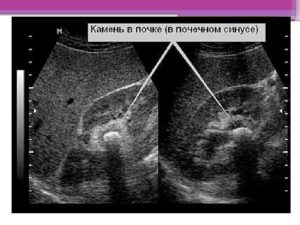

Если уплотнены элементы собирательной системы или почечный синус (внутрипочечная впадина с лоханкой и сосудами), это указывает на воспаление, опухоли, врожденные аномалии и т.д.

В зависимости от причины уплотнения локализуются в разных отделах ЧЛС:

- почечном синусе;

- лоханке.

Наибольшую опасность представляют деформации и уплотнения лоханки – воронкообразной полости, которая соединяется с мочеточником. При уменьшении ее просвета отток мочи в пузырь замедляется, что ведет к увеличению давления в органе.

Более нередко фиксируется уплотнение ЧЛС почек, но в ряде всевозможных случаев аномалия может затронуть и другие структуры, а именно, часто определяется уплотнение синусов почек.